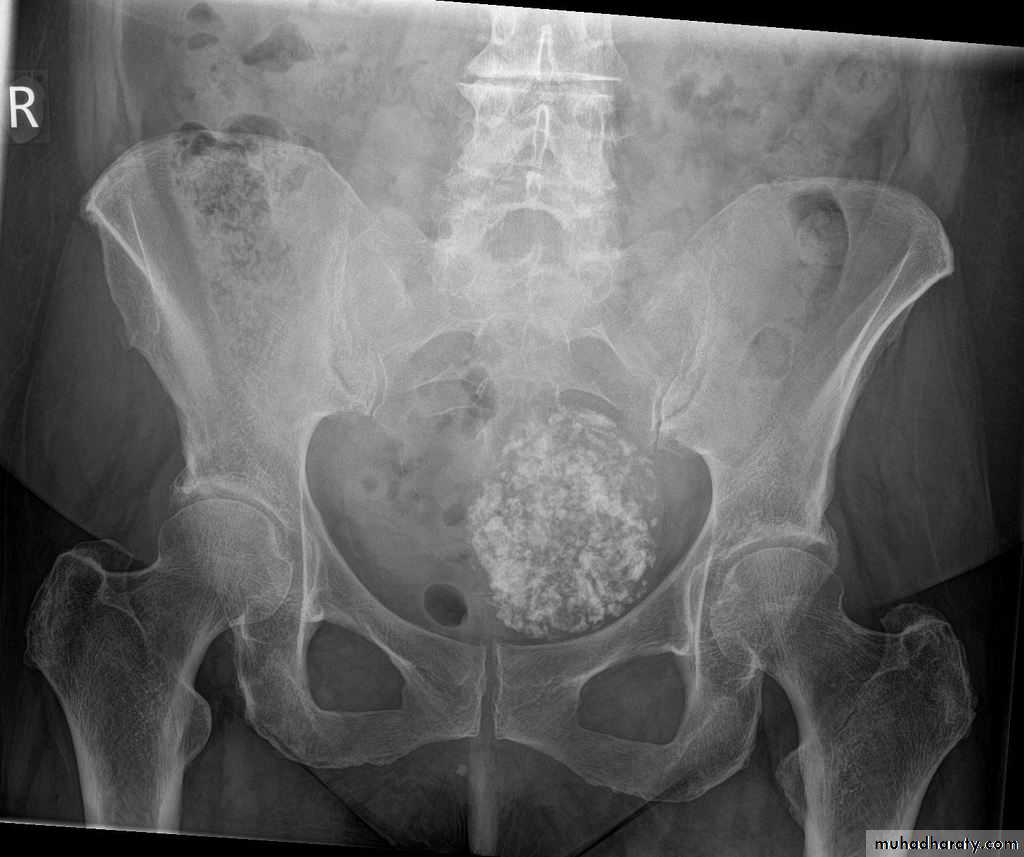

Schistosomiasis

Infestation by s.hematobium

Calcification is most important feature, mainly in bladder & lower ureters , but may involve whole ureters .

In early stage inflammation may cause cobble stone appearance.

Bladder capacity not affected.Ddgx of bladder calcification :

1. schistosomiasis .2.tumor , TB, …